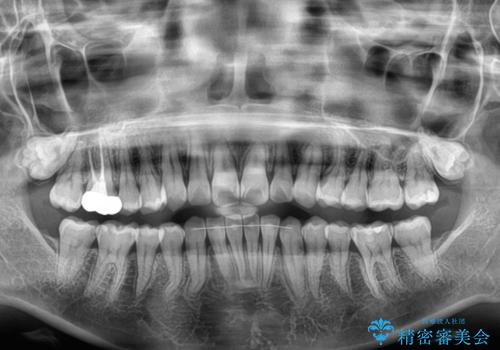

- 上下前歯のデコボコを改善したいとのことで来院された患者様です。

マウスピースを長時間装着し続ける自信はあまりないとのことでしたが、目立たない装置であれば頑張って装着するとのことで、インビザラインによる矯正治療を行うこととしました。

初めの1年くらいは何とか頑張って装着してくださいましたが、途中から変化をあまり感じられなくなり、日々の装着時間は徐々に短くなってしまいました。

前歯のデコボコはもっと改善できましたが、3年半が経過し、初診時と比べたら大幅に良くなったとのことで終了することとなりました。